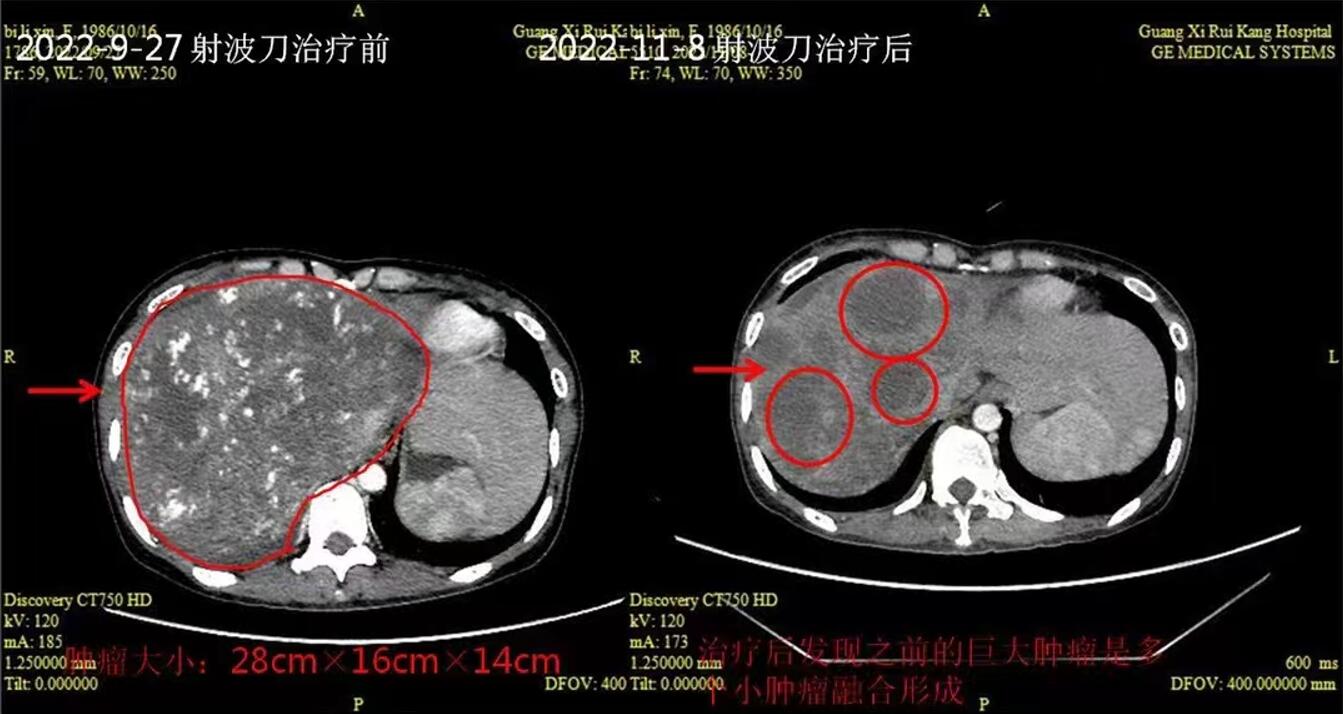

射波刀(CyberKnife)是当代社会最先进的全身立体定向放射治疗设备,具有精准度高、无伤口、无痛苦、无流血、无麻醉、恢复期短、预后好、患者治疗后即...